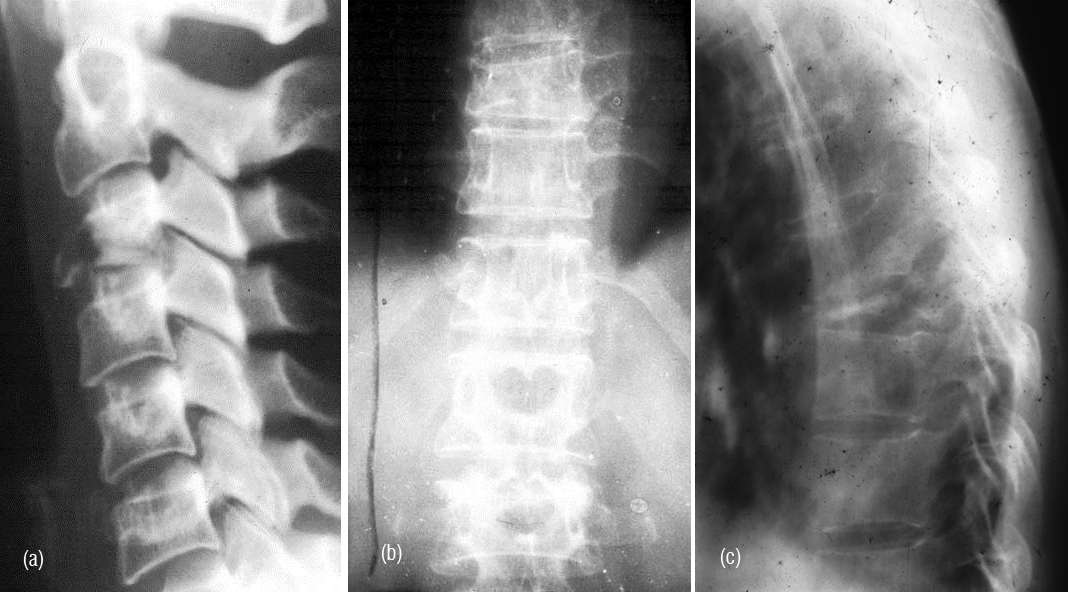

It is a solitary lesion and can be encountered in any bone. However, it is common in the spine. Most of the benign looking plasmacytomas when followed may develop into multiple myeloma eventually. Radiologically, a plasmacytoma is an expanding lytic lesion without any calcification or new bone formation. When it involves the vertebral body a compression fracture may be seen. When marked compression is seen vertebral plana is noted (Figure 1abc). To differentiate from metastasis, it is stated that in metastasis pedicles are involved earlier as they are vascular (2ab). However, when a large part of the body is involved in myeloma, pedicles also may be destroyed (Figure 3abc).

Figure 1a,b: Plasmacytoma with collapse of C3, T10. (c) Plasmacytoma – vertebra plana T8.

Figure 3abc: Plasmacytoma - Complete destruction of body of L3 including the posterior elements.